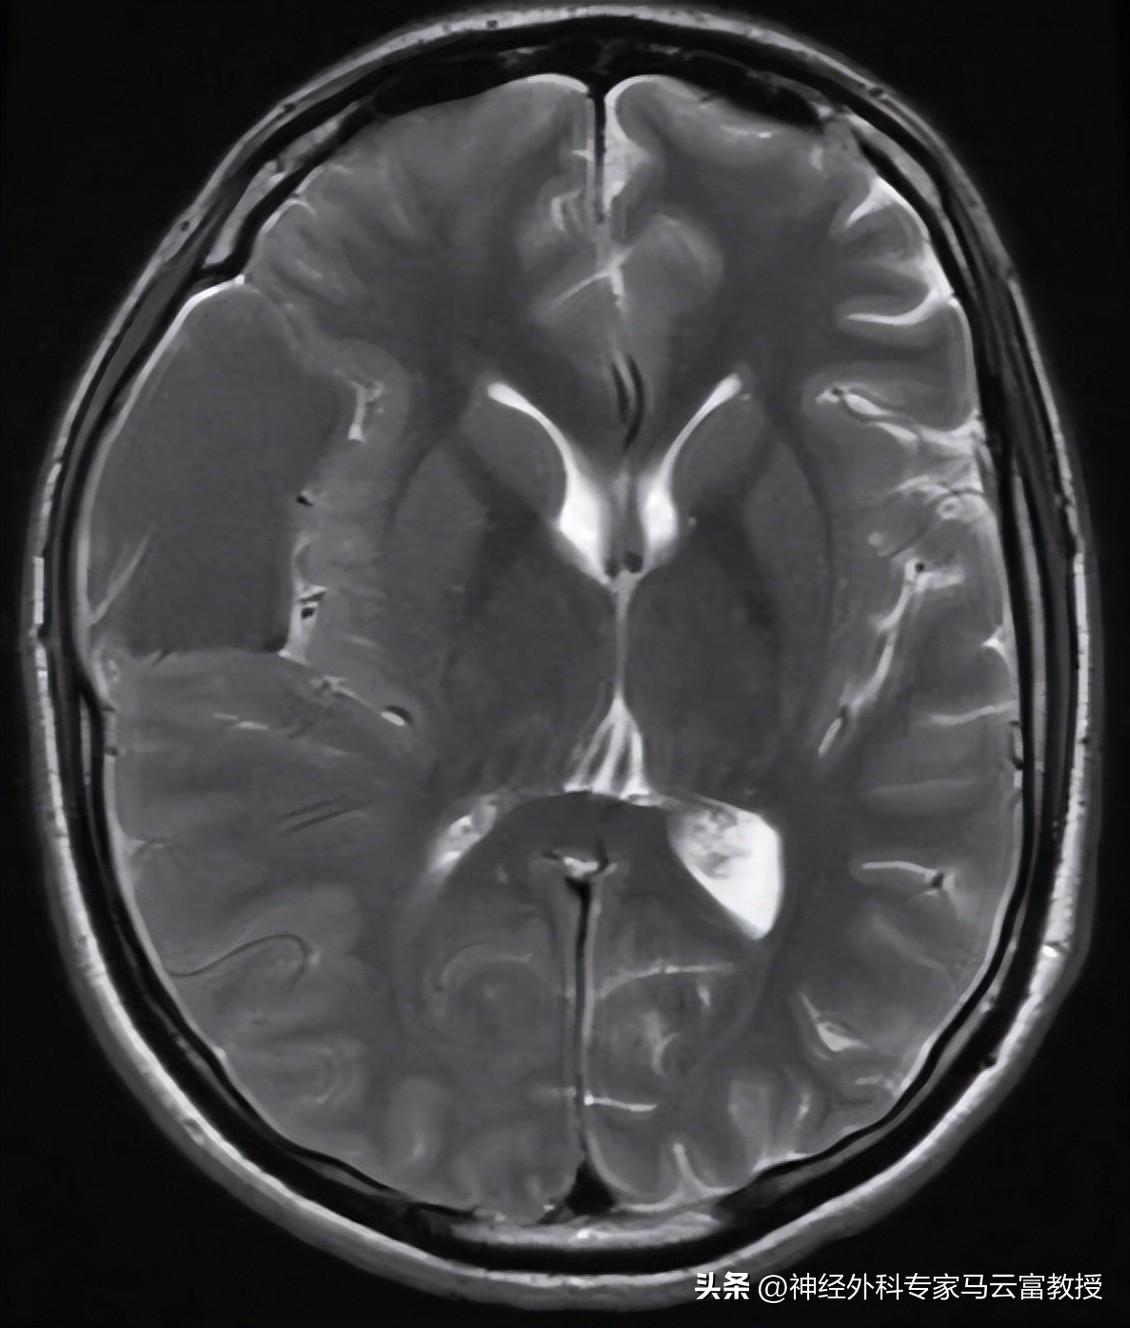

• 首選MRI(磁共振成像):這是金標準,能清楚看到囊腫的位置、大小和形狀。MRI沒有輻 射,對大腦細節顯示超級清晰。檢查時間半小時左右,躺在機器裏別動就行。

• CT掃描:如果MRI不方便,CT也能用。它更快,但有少量輻射,通常用於急診。